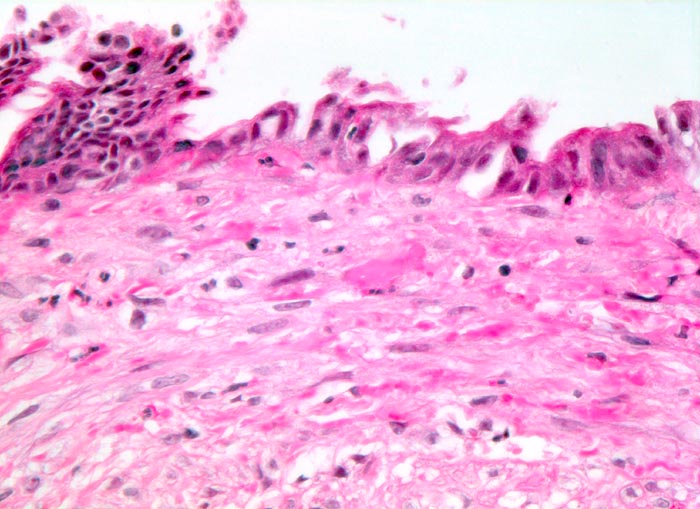

PathoPic – image database / PathoPic ID 3418 - chronische Cholezystitis

chronische Cholezystitis

Entzündung / Reparatur

Gallenblase

Das Schleimhautrelief ist abgeflacht. Das Epithel zeigt entzündlich bedingte regeneratorische Veränderungen mit vergrösserten Kernen. Das Stroma ist fibrosiert und minimal entzündlich infiltriert.

Wiederholte rechtsseitige Oberbauchbeschwerden.

Histologie

320